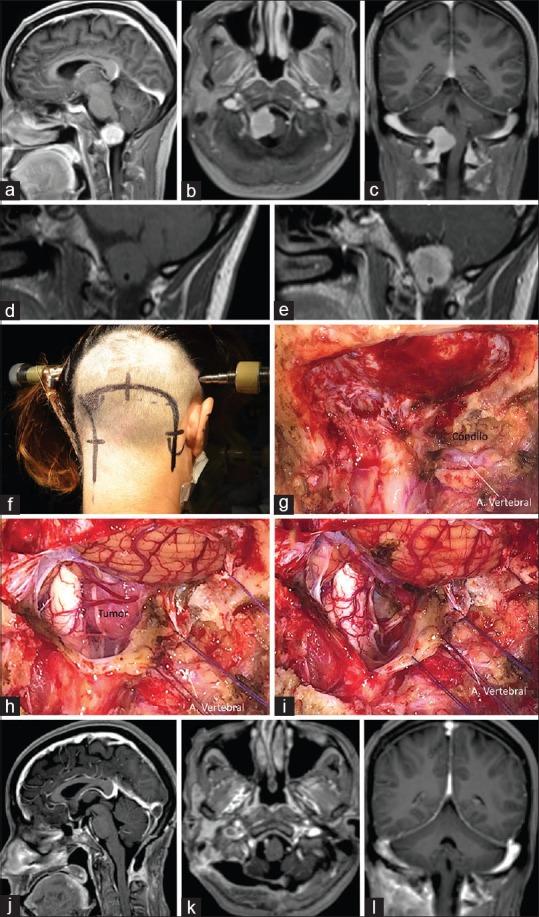

Between June 2005 and December 2016, 12 patients with foramen magnum meningiomas underwent microsurgical resection. Patients' age and gender, tumor localization (anterior or lateral), symptoms, approach, and postoperative results were analyzed.

Eight of the 12 patients were women. The average age of the patients was 47 years. In 8 patients, the tumor was located anteriorly and in 4 patients laterally. The main symptom was occipitocervical pain (8 patients), followed by tetraparesia (3 patients). For all the anterior foramen magnum meningiomas, an extreme-lateral transcondylar approach was performed. In cases where the tumor was lateral, an extreme-lateral retrocondylar approach was adopted. Total and subtotal resection was achieved in 10 and 2 patients, respectively. In the latter instances, a very small piece of tumor remained around the vertebral artery or inside the jugular foramen. Three patients exhibited postoperative cranial nerve XII palsy and 2 cranial nerve XI palsy. One patient experienced cerebrospinal fluid leakage.

Microsurgery for both anterior and lateral foramen magnum meningiomas can be performed safely and effectively. What is necessary is: (a) good anatomical knowledge of the region; (b) two-step muscle dissection to expose the suboccipital triangle and vertebral artery; (c) to adopt an extreme-lateral retrocondylar approach for lateral meningiomas, and an extreme-lateral transcondylar approach for anterior tumors; and (d) good microsurgical techniques.